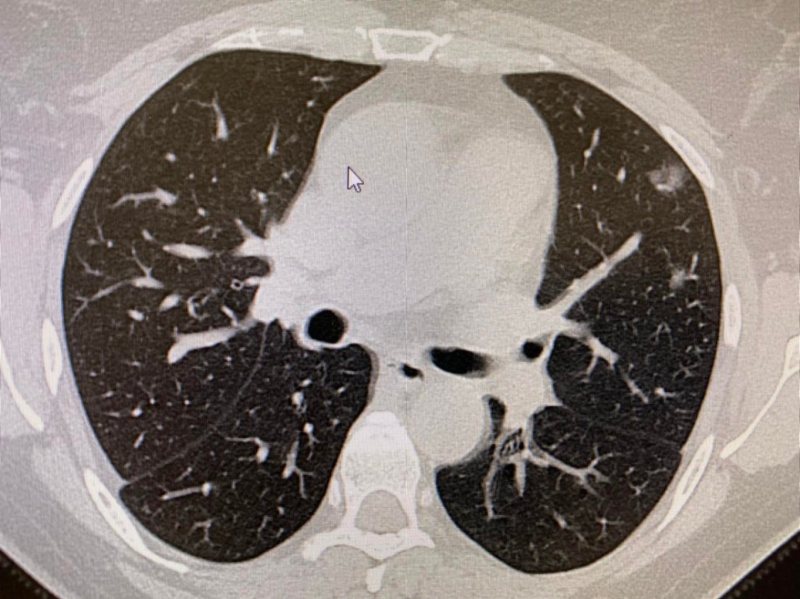

Dziewięciu było zaszczepionych. Na moją szczególną uwagę zwróciło jedno podwójne przyjęcie. 50 letni ojciec z 30 letnim synem mieszkający w jednym gospodarstwie domowym. Ojciec zaszczepiony dwiema dawkami szczepionki, syn nie został zaszczepiony. W TK klatki piersiowej. 50-letni Pacjent po szczepieniu - zmiany w płucach 1%, 30-letni syn bez szczepienia - zmiany w płucach 50%. Jest to jeden z wielu przykładów pokazujący, że szczepienia są ważne i należy się szczepić.

2 zdjęcie: 50% zajętych płuc.